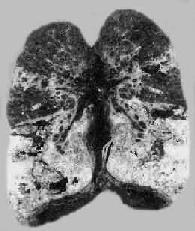

2)肺粟粒性结核病:又称血行播散型肺结核病。急性粟粒性肺结核病常是全身粟粒性结核病的一部分。偶尔,病变也可仅局限于两侧肺内。这是由于支气管周围肺门或纵隔淋巴结干酪样坏死破入附近的静脉(如无名静脉、颈内静脉、上腔静脉),含大量结核菌的液化物经右心和肺动脉播散至双肺所引起。肉眼观,双肺充血,重量增加,切面暗红,密布灰白或灰黄色粟粒大小的结节,微隆起于切面(图18-7),并显露于肺膜表面。

图18-7 肺粟粒性结核病

图中白色点状病灶为粟粒性结核灶